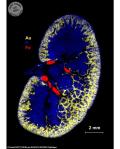

© Noël PINAUD/CNRS Photothèque